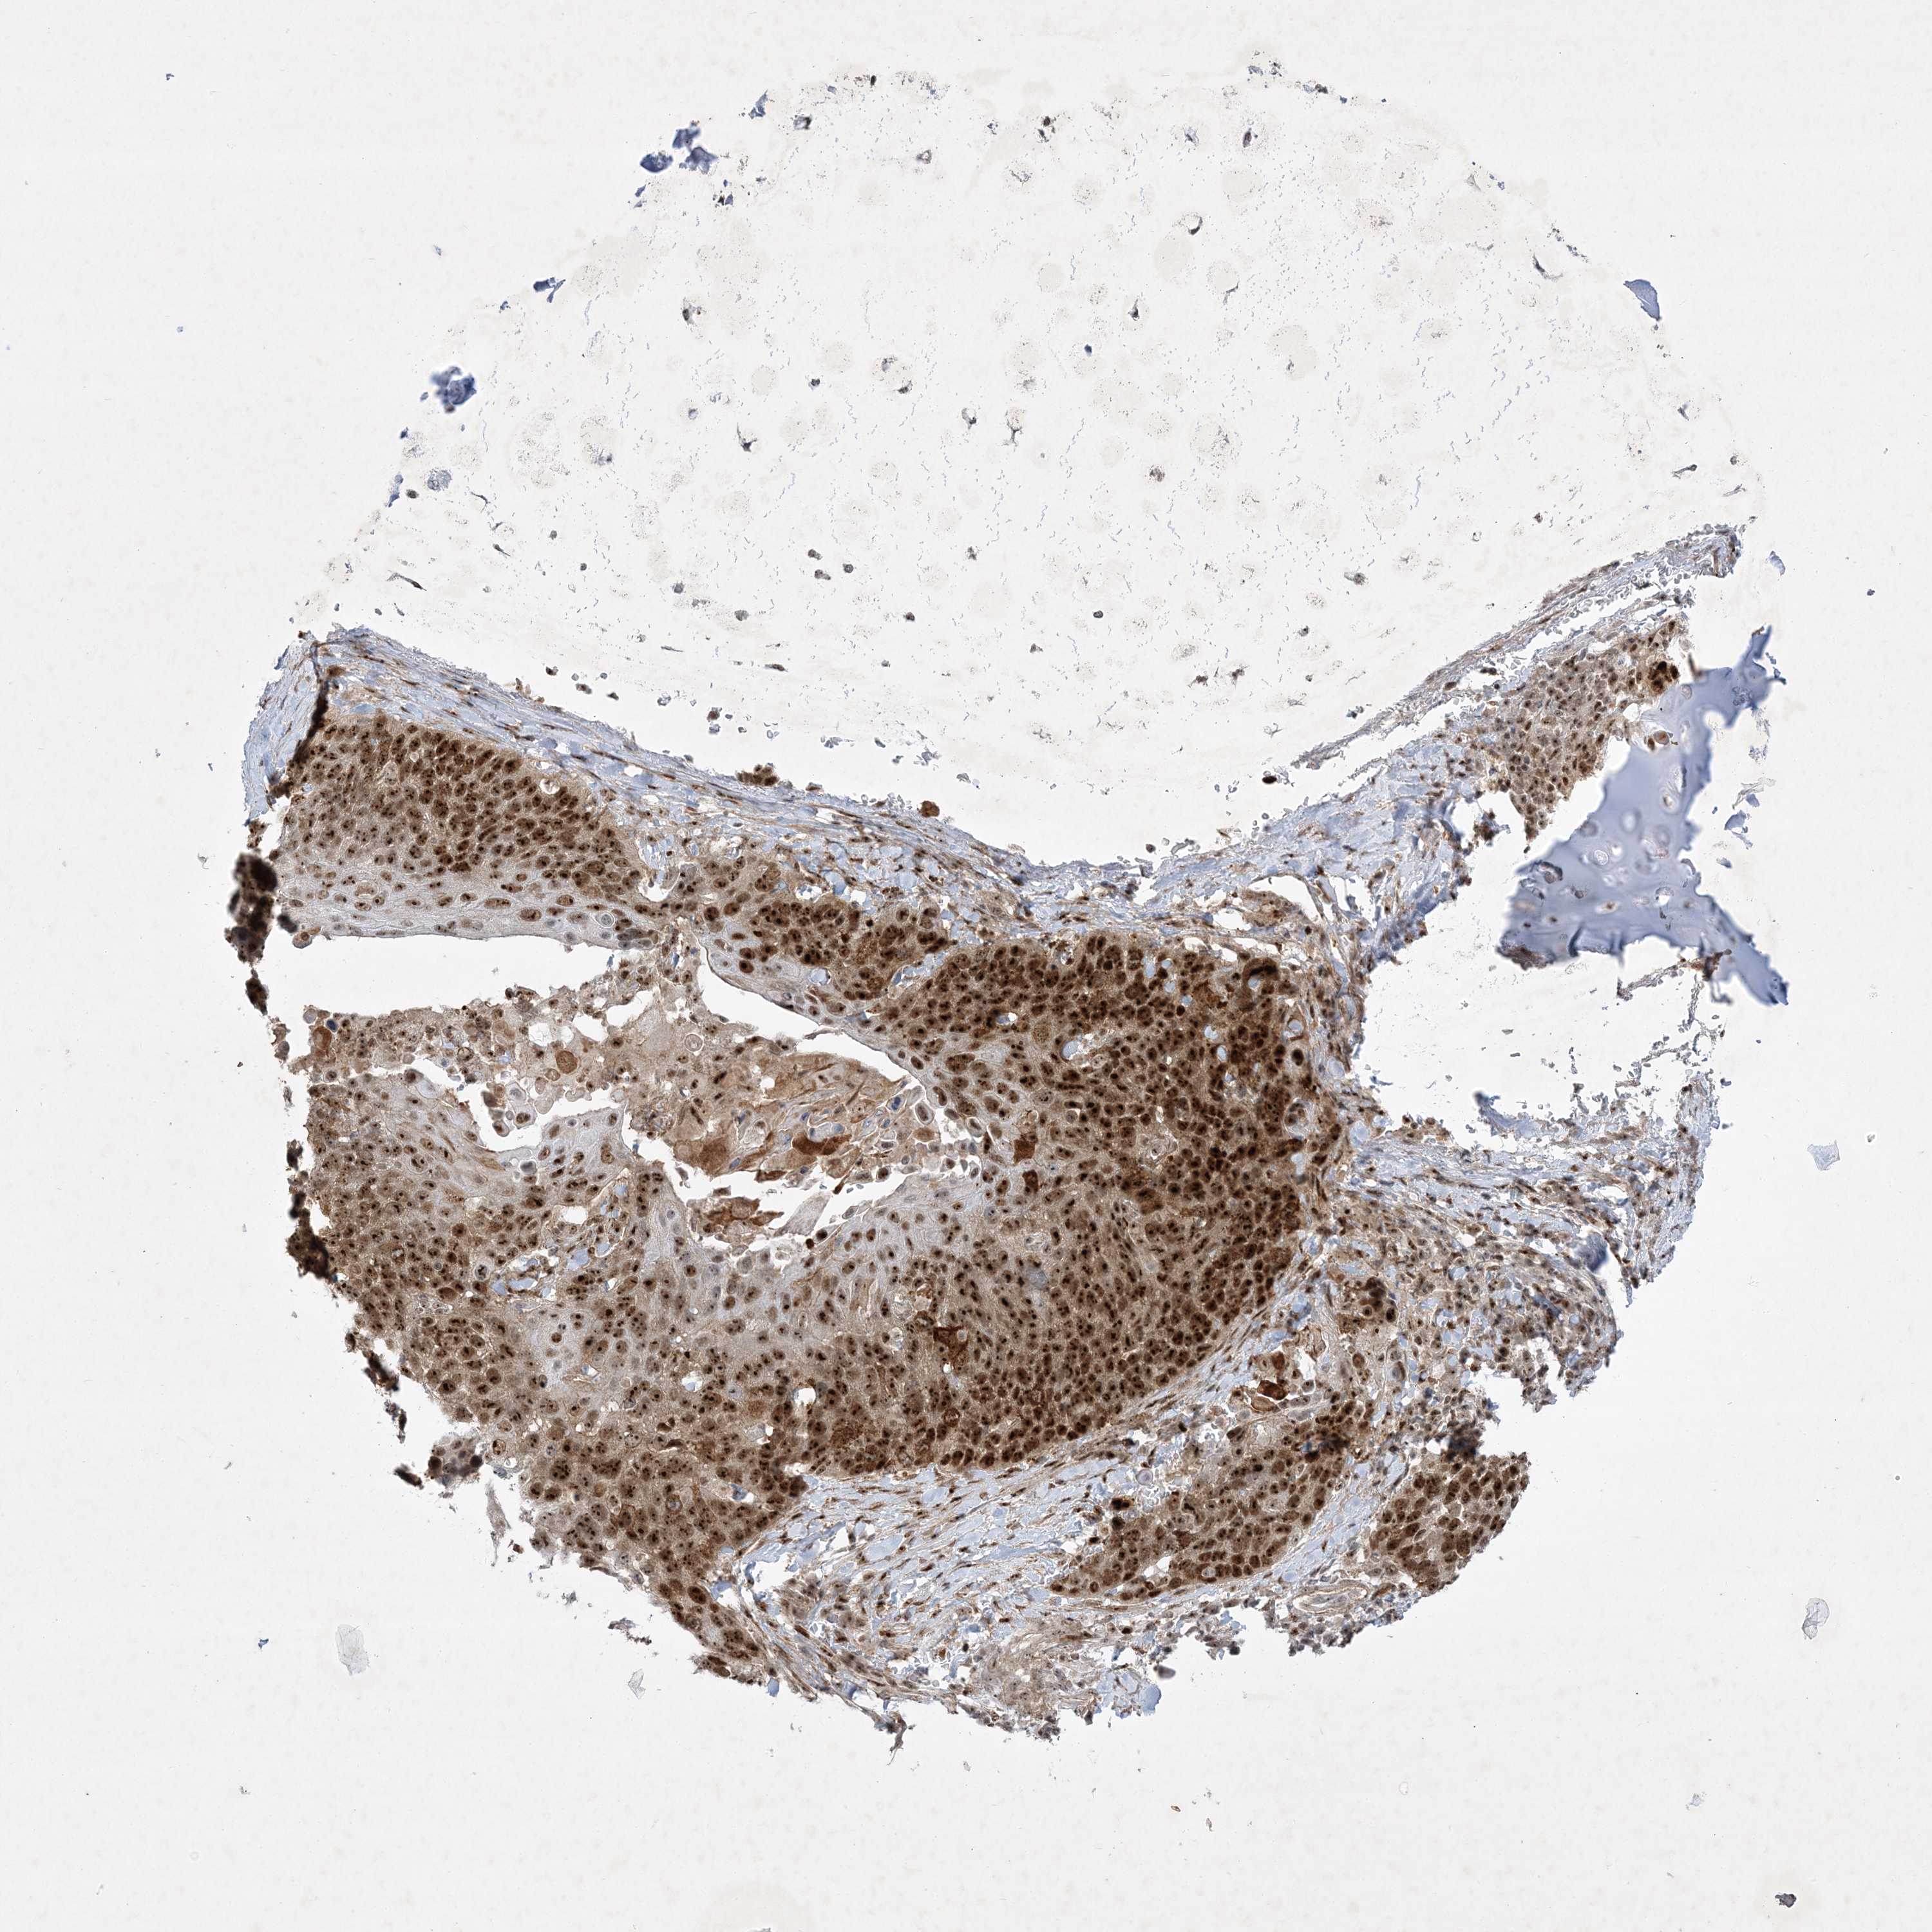

LUNG ADENOCARCINOMA (TCGA) - Interactive survival scatter ploti

The Survival Scatter plot shows the clinical status (i.e. dead or alive) for all individuals in the patient cohort, based on the same data that underlies the corresponding Kaplan-Meier plots. Patients that are alive at last time for follow-up are shown in blue and patients who have died during the study are shown in red.

The x-axis shows the expression levels (FPKM) of the investigated gene in the tumor tissue at the time of diagnosis. The y-axis shows the follow-up time after diagnosis (years). Both axes are complimented with kernel density curves demonstrating the data density over the axes. The top density plot shows the expression levels (FPKM) distribution among dead (red) and alive patients (blue). The right density plot shows the data density of the survived years of dead patients with high and low expression levels respectively, stratified using the cutoff indicated by the vertical dashed line through the Survival Scatter plot. This cutoff is automatically defined based on the FPKM cutoff that minimizes the p-score. The cutoff can be changed by dragging the vertical line or by entering a cutoff value in the square labeled "Current cut-off".

Under the Survival Scatter plot the p-score landscape (black curve; left axis) is shown together with dead median separation (red curve; right axis). Dead median separation is the difference in median mRNA expression between patients who have died with high and low expression, respectively. It is calculated as follows: median FPKM expression of dead patients with high expression - median FPKM expression of dead patients with low expression. This is intended to aid the user in visually exploring custom cutoffs and the associated p-scores and dead median separation.

Individual patient data is displayed and can be filtered by clicking on one or more of the category buttons on the top of the page. Categories describing expression level and patient information include: high, low, alive, dead, female, male and tumor stages. The scale of the x-axis can be toggled between linear and log-scale by clicking on the "x log" button. Mouse-over function shows TCGA ID, patient information and mRNA expression (FPKM) for each patient.

& Survival analysisi

Kaplan-Meier plots summarize results from analysis of correlation between mRNA expression level and patient survival. Patients were divided based on level of expression into one of the two groups "low" (under cut off) or "high" (over cut off). X-axis shows time for survival (years) and y-axis shows the probability of survival, where 1.0 corresponds to 100 percent.

NPM3 is not prognostic in Lung Adenocarcinoma (TCGA)

Stage:

Survival analysis

Current cut offi

Current cut-off shows the cut-off (FPKM) currently selected. It may be changed manually. When the current cut-off is changed, the vertical dashed line indicating cut-off, the interactive survival scatter plot and the Kaplan-Meier curve will be automatically adjusted to show results accordingly.

:

Best expression cut offi

Based on the FPKM value of each gene, patients were classified into two groups and association between prognosis (survival) and gene expression (FPKM) was examined. The best expression cut-off refers the FPKM value that yields maximal difference with regard to survival between the two groups at the lowest log-rank P-value. Best expression cut-off was selected based on survival analysis .

When clicking on this number, the vertical dashed line indicating cut-off, the interactive survival plot, and the Kaplan-Meier curve will be adjusted to show results based on the best expression cut-off.

: 31.57

Median expressioni

Median expression refers to the median FPKM value calculated based on the gene expression (FPKM) data from all patients in this dataset. When clicking on this number, the vertical dashed line indicating cut-off, the interactive survival plot, and the Kaplan-Meier curve will be adjusted to show results based on the median expression.

: N/A

Median follow up timei

Median follow up time refers to the median time (years) after diagnosis with this type of cancer, based on clinical data from all patients in this dataset.

P scorei

Log-rank P value for Kaplan-Meier plot showing results from analysis of correlation between mRNA expression level and patient survival.

N/A

5-year survival highi

5-year survival for patients with higher expression than the expression cutoff.

For melanoma and glioma, 3-year survival is shown.

5-year survival lowi

5-year survival for patients with lower expression than the expression cutoff.

TCGA RNA samplesi

RNA-seq data is reported as average FPKM (number Fragments Per Kilobase of exon per Million reads), generated by the The Cancer Genome Atlas (TCGA) .

Normal distribution across the dataset is visualized with box plots, shown as median and 25th and 75th percentiles. Points are displayed as outliers if they are above or below 1.5 times the interquartile range. FPKM values of the individual samples are presented next to the box plot.

Average pTPM 39.0

Number of samples 497